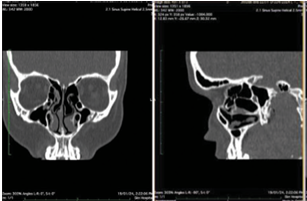

Case Series on Anatomical Variants of Paranasal Sinuses on Computed Tomography

[Piyush Srivastava, Pooja Shah]

A comprehensive understanding of paranasal sinus anatomy is crucial for clinicians. Traditional radiological techniques fall

short in detailing the nasal cavity and paranasal sinuses, which are now better visualized through computed tomography (CT)

imaging. CT provides detailed anatomical perspectives and identifies common anatomical variants. Recognizing these variants is

essential for the safe application of modern endoscopic sinus surgery, as it helps avoid potential complications. Multidetector CT

is increasingly used to image the paranasal sinuses before functional endoscopic sinus surgery. Multiplanar imaging, particularly

coronal reformations, offers accurate insights into sinus anatomy and its variations, which is vital before surgical procedures.

This study focuses on anatomical variants in the nasal fossae and paranasal sinuses observed through CT and highlights several

common anatomical variations, excluding broader anatomical variations such as deviated nasal septum and concha bullosa.

Keywords: Anatomic variants, computed tomography, functional endoscopic sinus surgery, paranasal sinuses, sinusitis